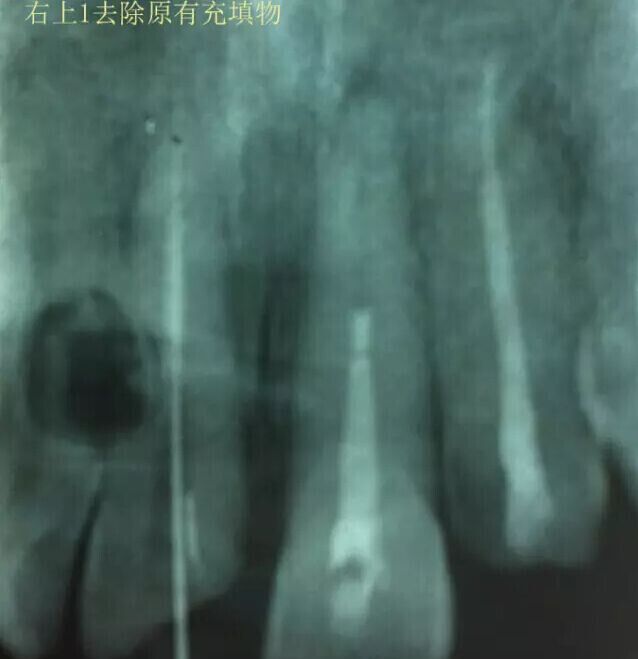

1,11 21去除根充物。

治療過程:經(jīng)患者同意。H銼去除11 21原有充填物,未發(fā)現(xiàn)明顯滲出物,無異味。K銼疏通根管,VDW根測儀測量長度,11牙20mmWL,21牙20mmWL。S3鎳鈦器械預(yù)備根管。(全程1%次氯酸鈉沖洗EDTA溶解潤滑)試尖片顯示牙膠未到位,繼續(xù)向牙根尖各2mm進入預(yù)備。吸潮紙尖吸干根管,登士柏樹脂根充糊劑輸送至根尖部位,以測量數(shù)據(jù)用牙膠尖冷充側(cè)壓充填根管,3M玻璃離子封閉根管口。不可用患牙啃咬硬物,擇日冠修復(fù)。

輔助檢查:插針X線片顯示根管內(nèi)充填物已經(jīng)取出。試尖片顯示牙膠尖未到位,繼續(xù)用K銼和機括向根尖預(yù)備。根充結(jié)束片顯示根充密實,無超充,無欠充。